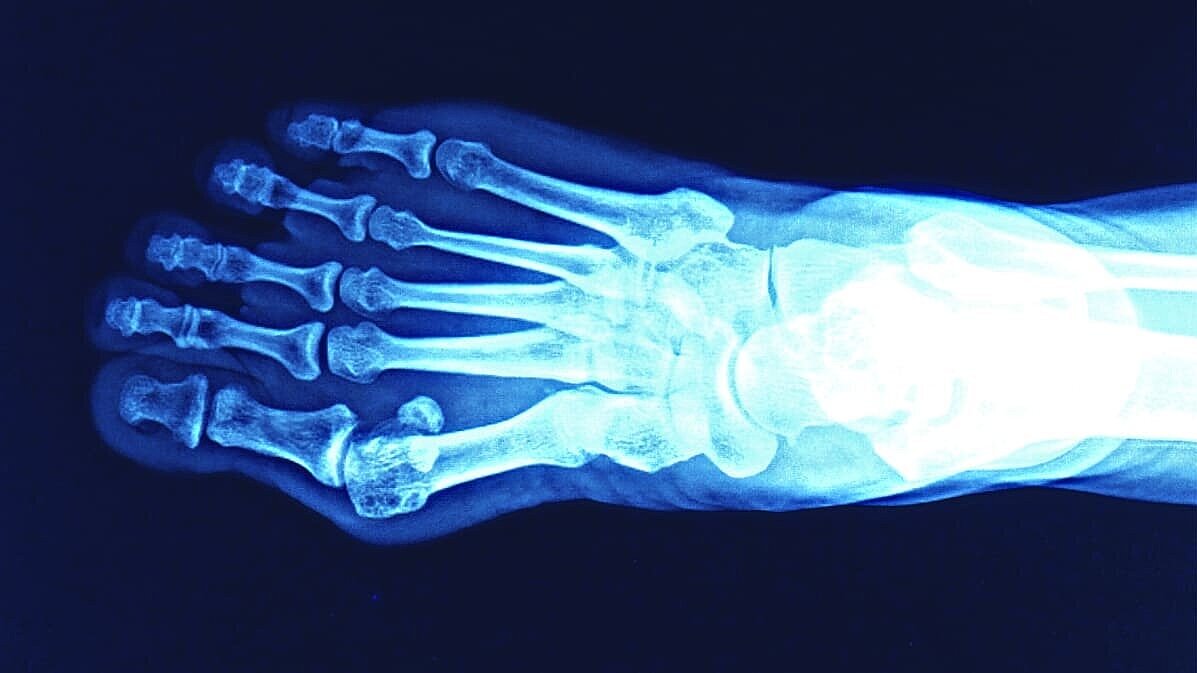

Röntgendiagnostik

Präzise Diagnostik für Ihre bestmögliche Behandlung

Unsere Röntgenabteilung bietet moderne bildgebende Verfahren, Ultraschall, wie digitales Röntgen, CT und MRT in Zusammenarbeit mit der Noris Radiologie individuell abgestimmt auf Ihre Therapie und medizinischen Bedürfnisse. Wir decken die konventionelle Röntgendiagnostik, insbesondere im Bereich des Bewegungsapparates, sowie die sonographische (Ultraschall-)Diagnostik ab. Der Schwerpunkt liegt auf orthopädisch-chirurgischen Untersuchungen, jedoch werden auch Fragestellungen aus anderen Fachgebieten zuverlässig bearbeitet.

• Konventionelles Röntgen (z. B. bei Frakturen, Gelenkerkrankungen, Vorsorgeuntersuchungen, prä- und postoperativen Fragestellungen, OP-Planung, Polytrauma nach Verkehrsunfällen)